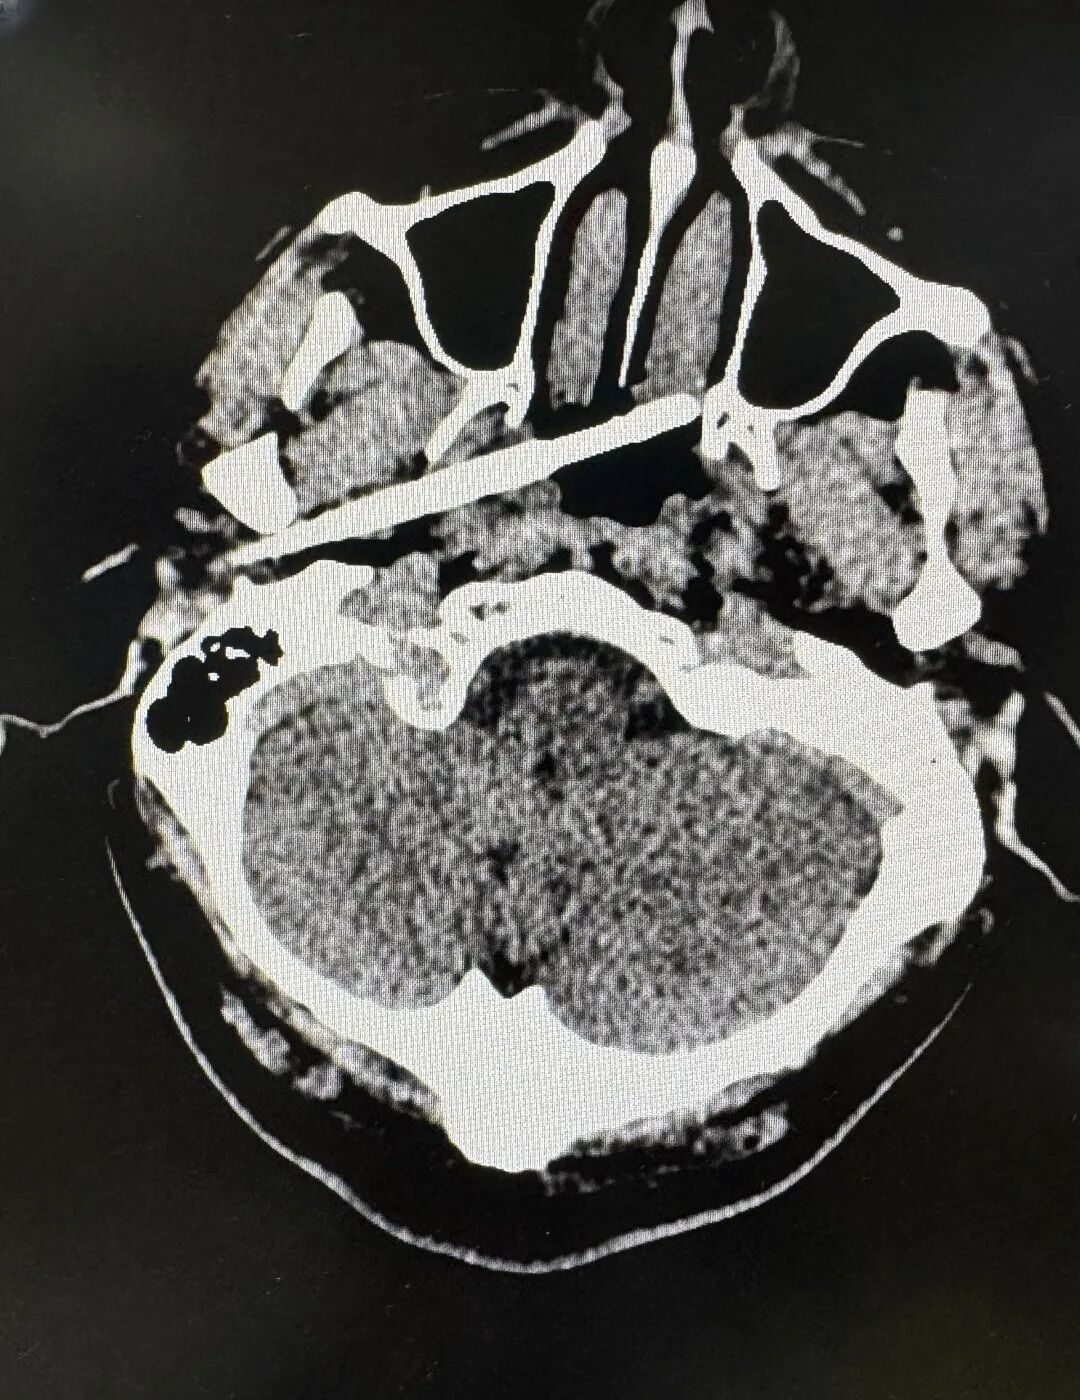

近日,南方医科大学珠江医院创伤中心成功救回了一名被筷子从耳部插入颅底的男子。据悉,筷子不仅穿透了耳部骨质,断端还残留在体内,筷子尖端距离颈内动脉仅5毫米,颈内动脉是大脑供血的主干线之一,一旦破裂,可导致瞬间大出血死亡,患者可能在短时间内死亡。

接诊后,创伤中心迅速启动严重创伤救治 “绿色通道”,召集耳鼻咽喉头颈外科、神经外科、影像诊断科、麻醉科专家进行多学科会诊(MDT),通过 CT 血管成像精准定位筷子位置及与血管的关系。

筷子入头影像